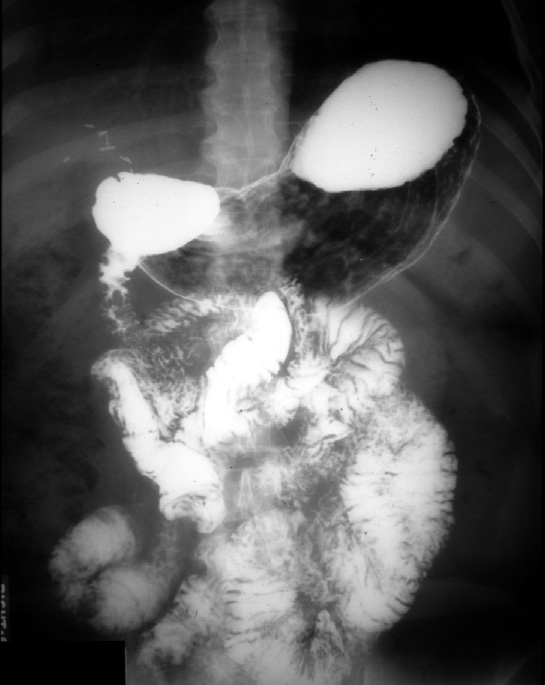

Note: This is an AP supine film after barium has been swallowed.

There are surgical clips in the right upper abdomen from a previous cholecystectomy

(removal of the gall bladder). The patient is lying on his back.

In the supine projection the barium will pool in the fundus and air will

rise to the antrum of the stomach.

Identify -- fundus, body, and antrum of stomach, duodenum, jejunum, ileum